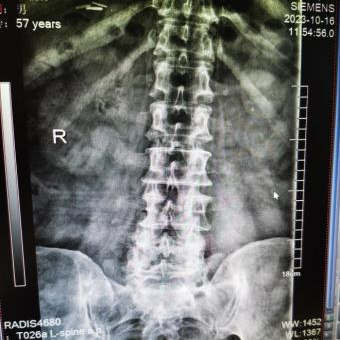

4月23日,贵州航天医院第58次晨读会由我院骨科副主任医师张艳金作学术交流,他以“加速康复指导下的快速手术”为题,详细讲解了老年股骨粗隆间骨折与儿童四肢骨折的临床诊疗难点,结合加速康复外科(ERAS)核心理念,重点阐述了ERAS理念在两大人群中的创新实践,实现患者入院后6至24小时内即可接受手术治疗。针对老年髋部骨折患者,提出通过多学科协作(MDT)与微创手术优化围术期管理,在确保安全前提下缩短术前等待时间,实施精准化麻醉及术后康复方案,可有效降低并发症发生率、改善患者生活质量和预后效果。在儿童骨折领域,强调微创术式与心理干预并行的双轨策略,既减少手术创伤对骨骼发育的影响,同时关注患儿心理疏导,实现生理功能与心理健康同步康复。并通过典型案例的影像学资料与随访数据,直观展示了ERAS理念指导下骨科治疗模式的创新成果。 贵州航天医院骨科 专家简介 赵学平 中共党员,骨科党支部书记、主任,主任医师 临床擅长:从事骨科临床工作30余年,对骨科常见疾病的诊治具有丰富的临床经验。 世界中医药联合会脊柱康复专业委员会常务理事,中华中医药学会整脊分会常务委员,中国中西医结合学会骨伤科分会肢体矫形功能重建与康复专家委员会常务委员,中国研究性医院学会骨科创新与转换专业委员会关节外科学组保髋工作委员会常委,中国康复技术转化及发展促进会骨外科与康复技术转化专业委员会常务委员,泛珠三角区域运动医学联盟(PPRD-SMA)理事会常务理事,中国研究型医院学会运动医学专业委员会委员,贵州省中医药学会整脊分会副主任委员,贵州省中西医结合学会银质针专业委员会副主任委员,贵州省康复医学会骨与关节专业委员会常务委员,贵州省人民医院骨科专科联盟常务理事,贵州省康复医学会骨内科专业委员会常务委员,中华医学会贵州省骨科学会委员,贵州省康复医学会脊柱脊髓专业委员会常务委员,贵州省运动医学分会委员,贵州省康复医学会骨与软组织肿瘤专业委员会委员,遵义市医学会创伤分会副主任委员,贵州省康复医学会骨内科专业委员会遵义地区分会常务委员,遵义市医疗事故鉴定、伤残鉴定、工伤鉴定、司法鉴定专家。 长期从事骨科临床研究及教学工作,在国家级、省部级杂志发表论文20余篇,SCI论文2篇,参与主编骨科专著2部,主持省部级科研项目2项,参与指导省部级、市级科研项目6项。 陈明勇 骨科副主任,副主任医师 临床擅长:从事创伤骨科工作约20年,对骨缺损、骨不连、骨肿瘤、肢体畸形等的肢体矫形重建及功能重建,慢性化脓性骨髓炎的根治治疗、糖尿病足的保肢治疗、快速康复理念(ERAS)下的老年骨折的诊治,四肢复杂骨折的诊治,四肢骨折等微创手术治疗具有丰富的临床经验。 2004年毕业于遵义医学院临床专业,曾在中国人民解放军总医院、广西医科大学第一附属医院、上海第六人民医院骨科进修。中国中西医结合学会骨伤科专业委员会横向骨搬移治疗糖尿病足及微血管网再生学组首届委员,遵义市医学会创伤分会常务委员。 瞿 辉 中共党员,骨科副主任医师 临床擅长:对骨科的常见病、关节外科、脊柱外科及运动医学疾病的诊治具有丰富的临床经验,熟练掌握骨科手术操作技术。 毕业于遵义医学院临床医学系,2005年前往广州中山大学第一附院骨显微医学部进修学习,2011年前往成都华西医院进修学习,并多次在省内外学习骨科相关知识,是中华医学会骨科分会会员。 赵兴东 骨科主任医师 临床擅长:擅长骨科的常见病及各种创伤、四肢骨折创伤修复、骨感染、手足疾病的诊治和手足体表畸形的矫形整复,熟练掌握骨科四肢骨病及创伤的手术操作技术,尤其在四肢关节复杂性损伤、手足外伤、组织缺损创面、难治创面的皮瓣修复方面及平足、高弓足矫形方面及四肢慢性疼痛诊治、康复方面具有丰富的临床经验。 硕士研究生,毕业于遵义医学院临床外科系,2015年前往山东省立医院手足外科进修学习;遵义市医学分会创伤分会第一、二届委员,遵义市手外科医学会第二委届员会常务委员;在省级及省级以上期刊发表文章9篇,参编著作2部,参与主持并完成市级课题1项,参与市级课题2项、省级课题1项。 张艳金 中共党员,骨科副主任医师 临床擅长:从事骨外科工作16年,对复合伤、多发伤的救治、四肢骨干骨折、关节周围骨折、骨肿瘤、骨髓炎等诊治具有丰富的临床经验。 中共党员,硕士研究生,2006年本科毕业于山西医科大学第二临床医学院,2011年研究生毕业于北京军区总医院;在“老年COPD患者合并髋部骨折的诊治”国际合作课题组研究两年,在老年髋部骨折的诊治方面具有丰富的经验,并发表论文6篇;主持遵义市级课题1项,承担遵义医科大学的临床教学工作,获得遵义医科大学优秀带教老师荣誉。编撰有《骨科疾病诊疗精粹》一书,开展2项新技术,编撰地方规范《务川自治县创伤骨科常见疾病诊疗规范》一书。 张俊凯 骨科副主任医师 临床擅长:从事骨科临床工作28年,对创伤骨折、骨感染、骨缺损、骨不连等外科诊治,四肢骨折的微创手术治疗,四肢复杂骨折(如关节内粉碎性骨折、多发骨折等)的损伤控制及手术治疗等具有丰富的临床经验。 1995年毕业于遵义医学院临床专业,2009年前往复旦大学附属医院骨科进修1年。 卢懿明 中共党员,骨科副主任医师 临床擅长:从事骨科工作18年,对创伤骨折、四肢骨折的微创手术治疗、四肢复杂骨折(如关节内粉碎性骨折、多发骨折等)的损伤控制及手术治疗,尤其是髋部骨折的PFNA等微创技术,踝关节骨折、膝关节周围骨折的Mipo微创技术等具有丰富的临床经验,开展了4项新技术,发明6项新型专利技术。 2005年毕业于遵义医学院临床专业,2017年,前往南方医科大学第三附属医院骨科进修半年,回院后运用Mipo技术对骨干骨折及干骺端骨折的治疗技术,同时积极开展骨盆骨折、髋臼骨折腹直肌外侧切口的应用;发表了多篇专业论文,经常参与省内外学术交流会授课,获得医院荣誉称号多个。 邬夏荣 骨科副主任医师 临床擅长:从事骨科工作16年,对四肢复杂骨折、骨肿瘤的诊治,尤其是足踝创伤、慢性踝关节损伤、平足症等诊疗具有丰富的临床经验。 2006年毕业于遵义医科大学临床医学专业,曾在陆军军医大学西南医院进修学习,发表多篇骨科学术论文。 余德怀 中共党员,骨科副主任医师 临床擅长:从事骨科工作10余年,对运动医学、骨关节、脊柱外科常见病、多发病的诊治具有丰富的临床经验。 硕士研究生,2011年毕业于遵义医学院临床医学专业,曾前往遵义医科大学附属医院运动医学专业进修学习;是贵州省医学会运动医学分会青年委员,西部关节镜联盟委员;发表多篇骨科学术论文。 冯 乾 骨科副主任医师 临床擅长:从事骨科工作近20年,熟练掌握骨科多发病及常见病的诊治,尤其对脊柱退变性疾病的诊断及治疗具有丰富的临床经验,主要研究脊柱微创相关治疗方式,能熟练开展椎间孔镜及UBE。 曾前往北京大学第三医院进修学习疼痛及椎间孔镜、首都医科大学友谊医院专业进修脊柱内镜;是贵州省康复医学会第三届脊柱脊髓专业委员会委员;发明专利3项、发表脊柱外科专业论文多篇。 赵小锋 中共党员,骨科副主任医师 临床擅长:从事骨科临床工作11年,对骨科常见病、多发病诊疗有较为丰富的临床经验,擅长脊柱相关疾病诊断及治疗,尤其是颈、腰、腿疼痛疾病诊断及治疗,擅长胸腰椎骨折微创经皮穿刺内固定术、经皮穿刺椎体成形术、经皮穿刺脊柱内镜下腰椎间盘摘除术、单纯开创腰椎间盘摘除术、腰椎滑脱复位椎间植骨椎融合内固定术、腰椎管狭窄减压融合内固定术及人工髋、膝关节置换术等。 2012年毕业于遵义医学院外科学专业硕士研究生,2019年参加“遵义市115医学人才精英计划”于上海交通大学第一附属医院培训学习,2023年于北京大学第三人民医院脊柱外科进修学习,曾获得遵义市优秀医师荣誉称号。 遵义市手外科第一届委员,遵义市医学会创伤分会第一届委员,遵义市医学会创伤分会第二届委员,贵州省康复医学会第三届脊柱脊髓专业会委员,遵义市医学会烧伤与整形外科学分会委员,发表论文5篇,其中国家级核心期刊1篇,SCI论文1篇,主持市级课题1项并结题,参与市级课题2项。 贵州航天医院骨科 简介 基本情况 贵州航天医院骨科组建于20世纪60年代,前身是以创伤和断肢(断指)再植闻名于世的上海市第六人民医院骨科,中国断肢(断指)再植的奠基者、中科院院士陈仲伟等著名专家、学者多次莅临科室指导医疗、教学,是贵州省最早拥有专业骨科技术科室之一,在70年代开展了贵州省首例断肢(断指)再植手术。组建50余年来,诊治患者已逾百万,挽救了无数的伤病员,成为了保障遵义地区人民群众健康的重要支撑。 经过几代人的不懈努力,今天的骨科,已由创伤骨科发展至骨病、骨肿瘤、骨结核等领域,现有脊柱外科、关节外科、四肢创伤、手足外科四个亚专科,成为了集医疗、教学、科研于一体的综合学科,是贵州省临床重点专科、遵义市临床重点专科、遵义市骨科临床医学中心、遵义市基层骨科专科联盟理事长单位。 科室目前开放床位110张,共有医护人员50余人,副高级以上专家18人,硕士研究生15人。拥有一流骨科医疗设备多台,每年不定期选派优秀技术骨干到全国各大知名医学院校进修、学习、参观、交流,并邀请国内、国外知名专家教授来院进行交流、指导,通过不断引进国内外先进的诊疗技术,科室医疗技术水平稳步提升,为广大人民群众提供了优质的医疗服务。 专科特色 骨一科 (一)骨缺损、骨不连的肢体与功能重建 胫骨横向骨搬移技术治疗糖尿病足: (二)慢性骨髓炎的根治治疗 (三)肢体缺血性疾病如糖尿病足、脉管炎的保肢治疗 (四)皮瓣修复 (五)复杂创伤的治疗 (六)老年髋部骨折及小儿骨折快速手术 老年髋部骨折: 骨二科 (一)胸腰椎骨折微创经皮椎弓根螺钉固定术 (二)老年性骨质疏松性患者腰椎滑脱脊柱内固定术(骨水泥螺钉) (三)V形双通道脊柱内镜技术(VBE)腰椎融合术治疗腰椎退行性疾病 (四)老年性骨质疏松性骨折(PVP/PKP)术 (五)人工髋关节置换术 (六)双侧股骨头坏死人工全髋关节置换 (七)右侧全髋置换术后假体周围骨折翻修 (八)人工膝关节置换术 (九)人工膝关节假体松动翻修 (十)关节镜技术 传统手术切口 关节镜技术切口 诊疗范围 骨一科 1.四肢创伤、矫形。 2.手、足踝外科。 骨二科 end